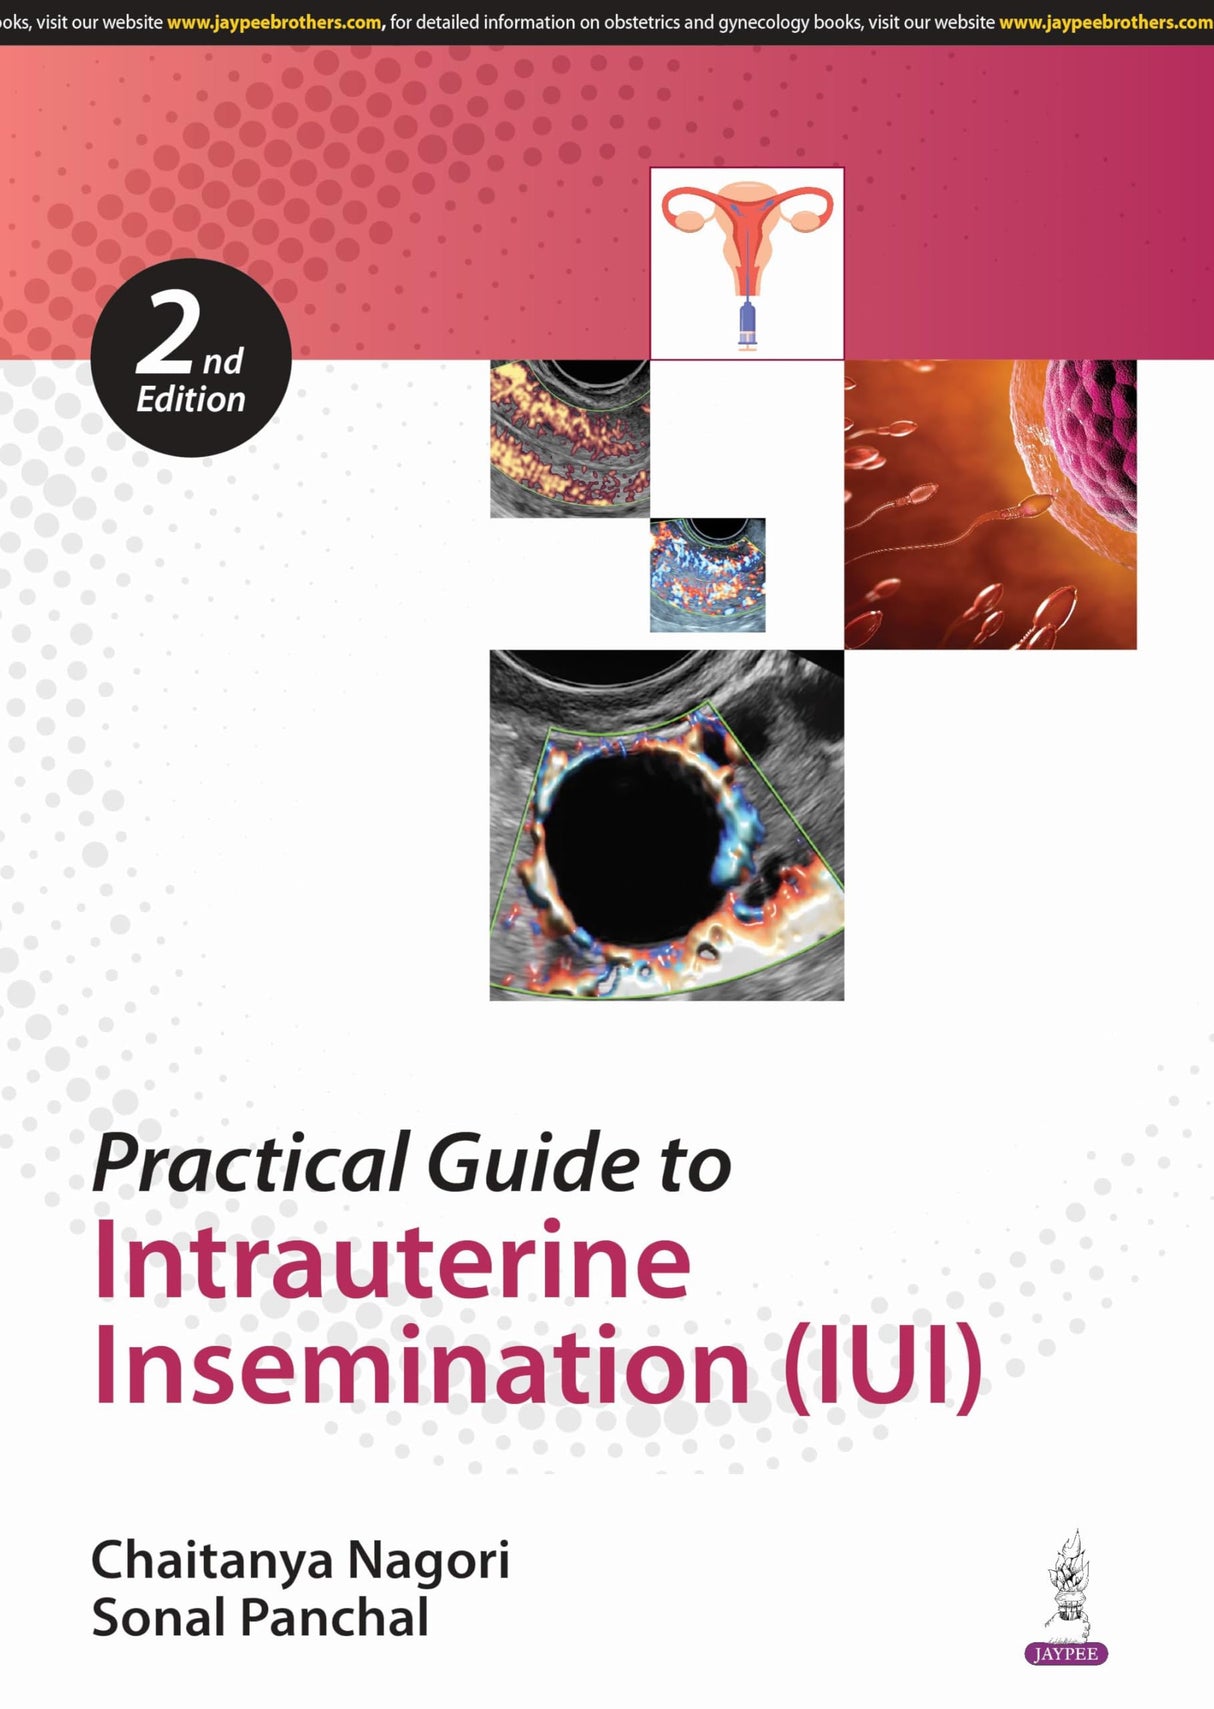

Beginning with discussion on counselling and diagnostic work-up before IUI, the next chapters cover indications and ultrasound. The following sections examine ovulation, timing of IUI, techniques, luteal phase support, complications, and factors affecting success. The final chapter discusses sperm preparation.

The text is further enhanced by clinical images and figures.